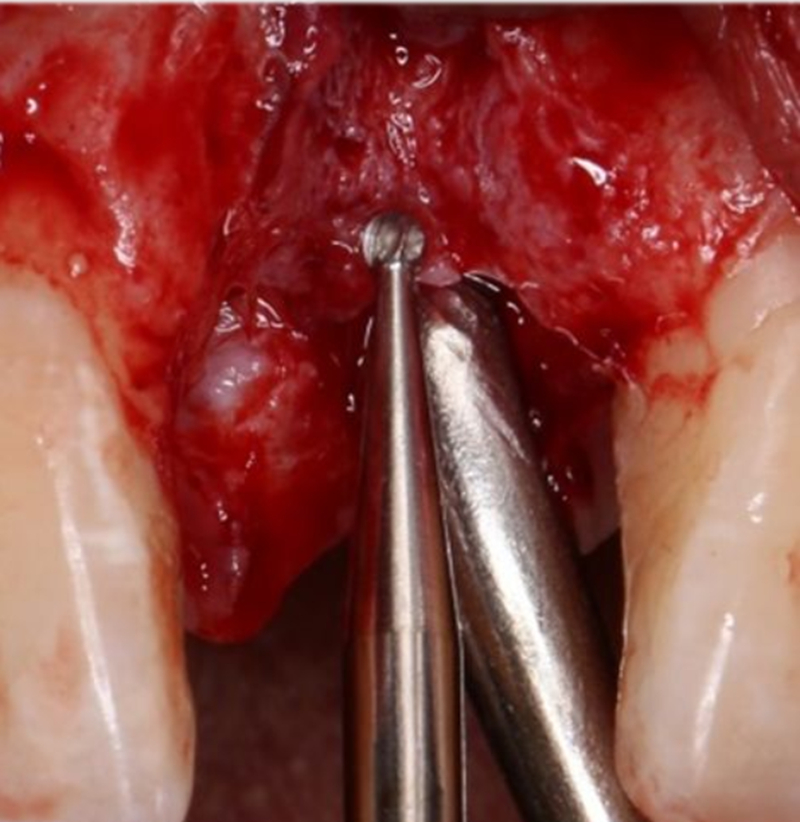

定點

1.4mm小球鉆定點 △

2.3mm中號球鉆打開皮質(zhì)骨

在易植美實時導(dǎo)航系統(tǒng)中,計算機引導(dǎo)球鉆精準按照術(shù)前設(shè)計定位